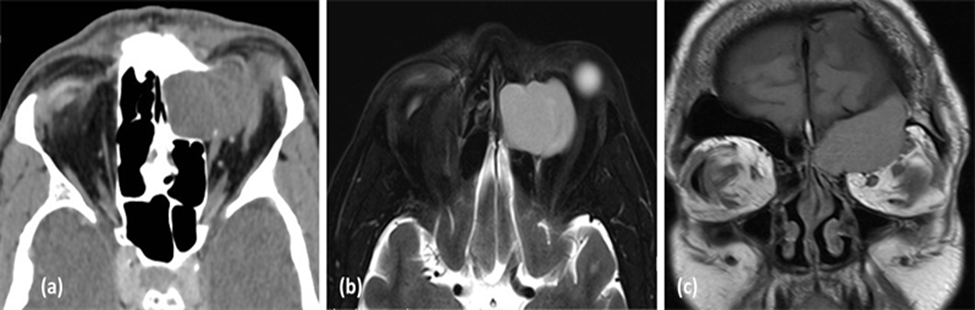

• Hình ảnh u nhầy trên MRI:

-Giai đoạn đầu (U chứa nhiều nước): Giảm đậm độ thì T1, tăng đậm độ thì T2

-Giai đoạn sau (Tích tụ protein): Tăng đậm độ trên cả T1 và T2

(a) Hình ảnh CT scan lát cắt axial cho thấy u nhầy xoang trán- sàng trái gây tiêu xương thành trong ổ mắt trái và (b) Hình ảnh MRI lát cắt axial và (c) nhát cắt coronal trên cùng 1 bệnh nhân cho thấy hình ảnh xâm lấn vào ổ mắt, gây ra trên lâm sàng bệnh nhân có lồi mắt trái. (Nguồn: Sarah A. AlMansour1, Ali A. AlMomen2 The Endonasal Endoscopic Management of Paranasal Sinuses Mucoceles (2021))